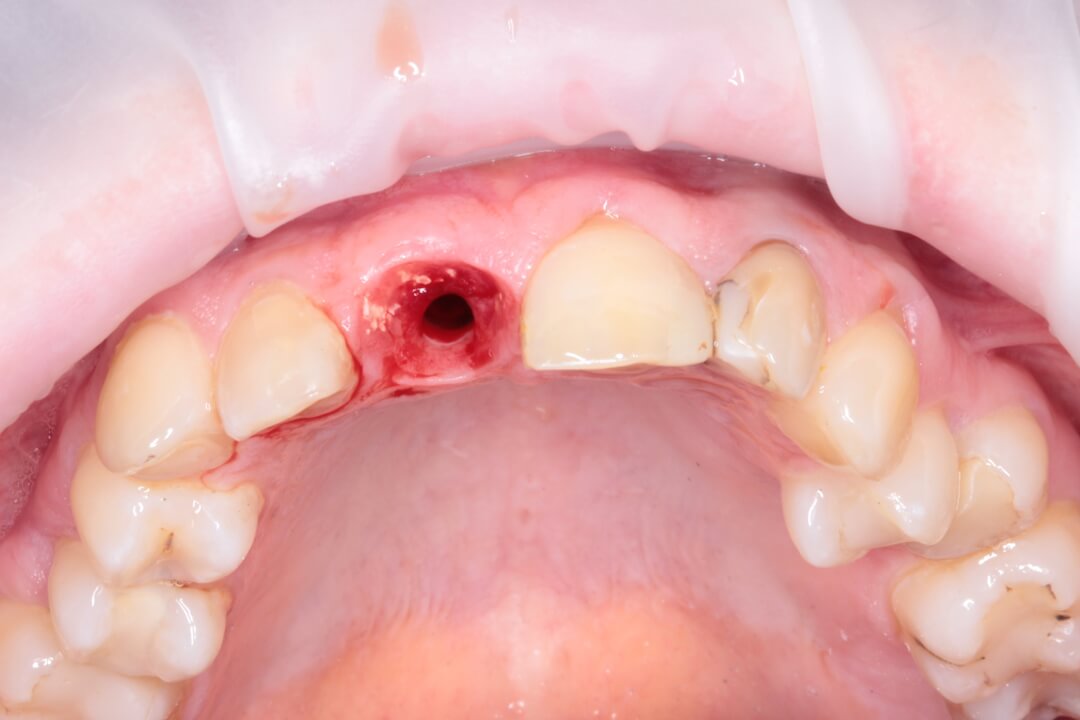

Рис. 1 Исходная ситуация.

Зуб был атравматически удален фрагментированием на части с помощью пьезохирургического аппарата и элеватора для максимального сохранения объема костной ткани в месте будущей дентальной имплантации. Во время экстракции врач сохранил целостность вестибулярной стенки альвеолы. Восстановление дефекта мягких тканей в данной области проводилось при помощи туннельной технологии субэпителиальным небным десневым трансплантатом . Устранение дефекта слизистой оболочки и десен способствует стабильному высокоэстетическому результату лечения. После этого хирург осуществляет наращивание костной ткани в вестибулярной области с использованием твердых частиц остеопластического материала. Для предотвращения попадания костного материала на внутреннюю часть имплантата врач устанавливает формирователь десны. Учитывая то, что пациентка по профессии учитель и впереди у нее было много ответственных мероприятий, было принято решение изготовить временную коронку на дентальный имплант непосредственно во время операции, так как все необходимые для этого условия были соблюдены и была такая возможность для этого.